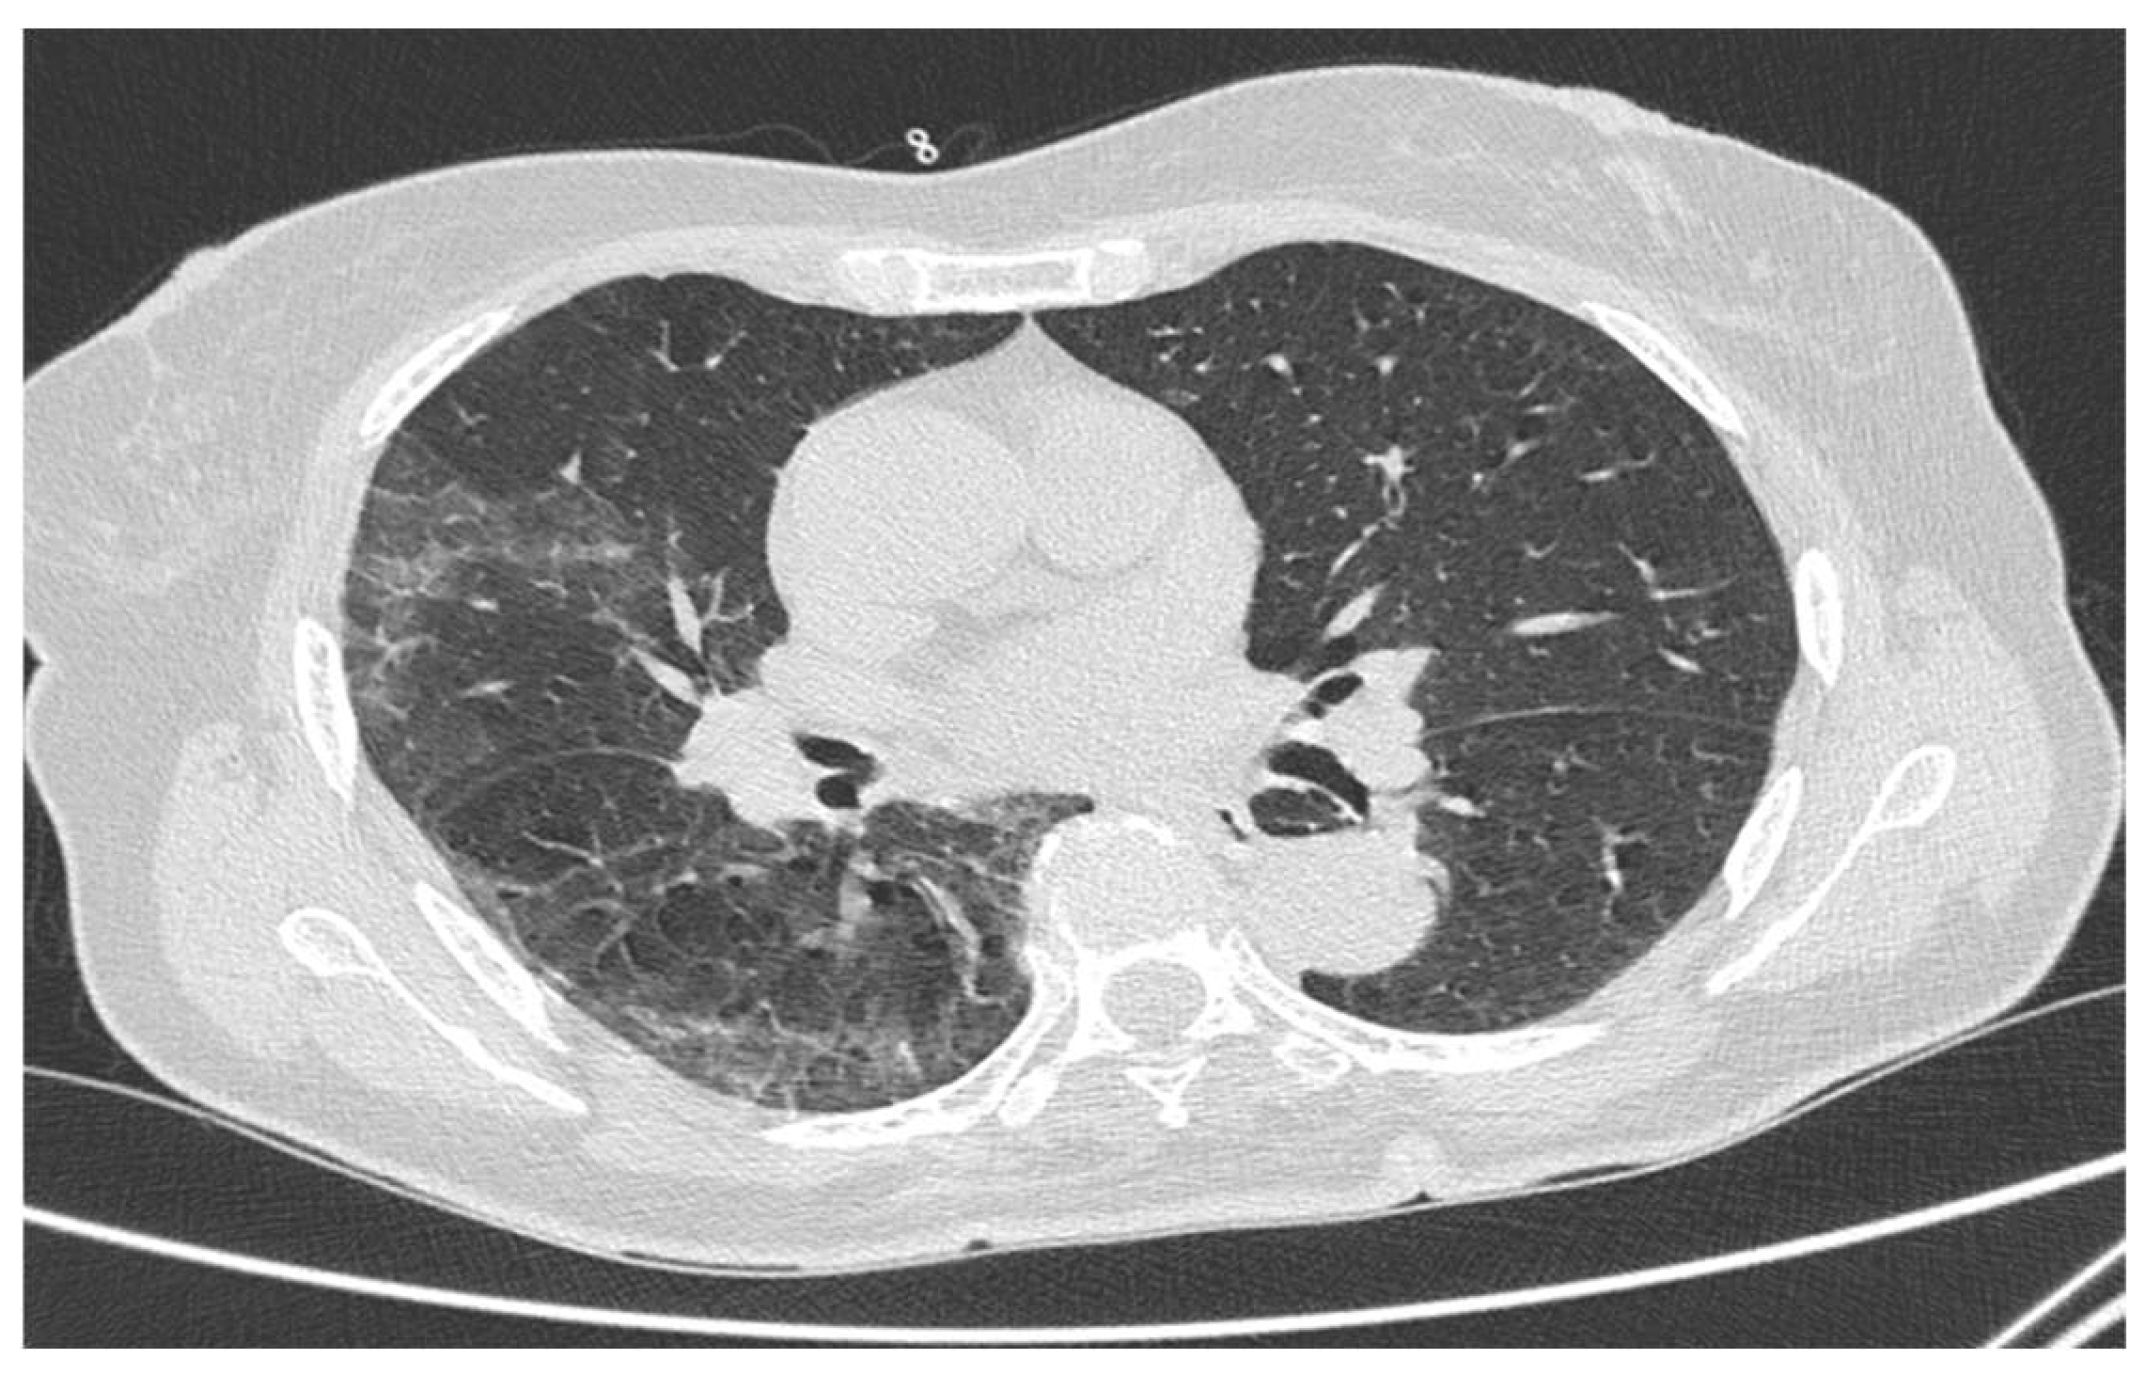

2.2. Chest HRCT Acquisition and Examination

3. Results